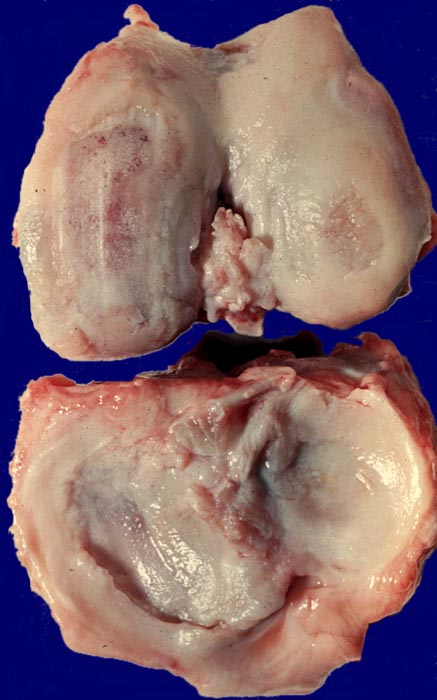

• Deformierte Gelenkfläche.

• Weitgehendes Fehlen des hyalinen Gelenkknorpels.

Makroskopie

Befund

Pathologischer Befund

Normalbefund